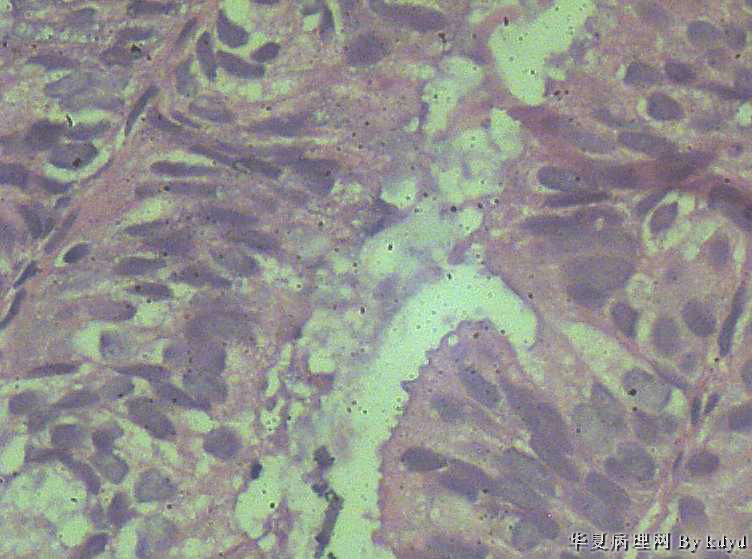

51岁,停经一年后,阴道流血。行宫腔诊刮。

B超示:宫腔有一赘生物大小1.5*2.5大小。

肉眼观:少许粘液及碎组织。(全包)

疑问:1。腺体呈复杂性增生伴不典型增生?

2。腺体有分泌反应,有些腺体看上去又像是宫颈的腺体(手术医生说是宫腔取的)?

3。怎样报告???

• 腺体非典型增生?是宫腔还是宫颈??图1

• 腺体非典型增生?是宫腔还是宫颈??图2

图2

• 腺体非典型增生?是宫腔还是宫颈??图3

图3

• 腺体非典型增生?是宫腔还是宫颈??图4

图4

腺体密集,有背靠背、共壁,有乳头状结构,有核异性性,有病理核分裂:

子宫内膜中-重度不典型增生,癌变不能排除

宫内膜样癌(高分化)。组织腺体拥挤、背靠背、血管纤维轴心乳头状,间质细胞消失代之纤维。

腺癌,内膜和宫颈的很难区分,可结合免疫组化,ER\PR,上色就应该是内膜来源,不上色就是宫颈了